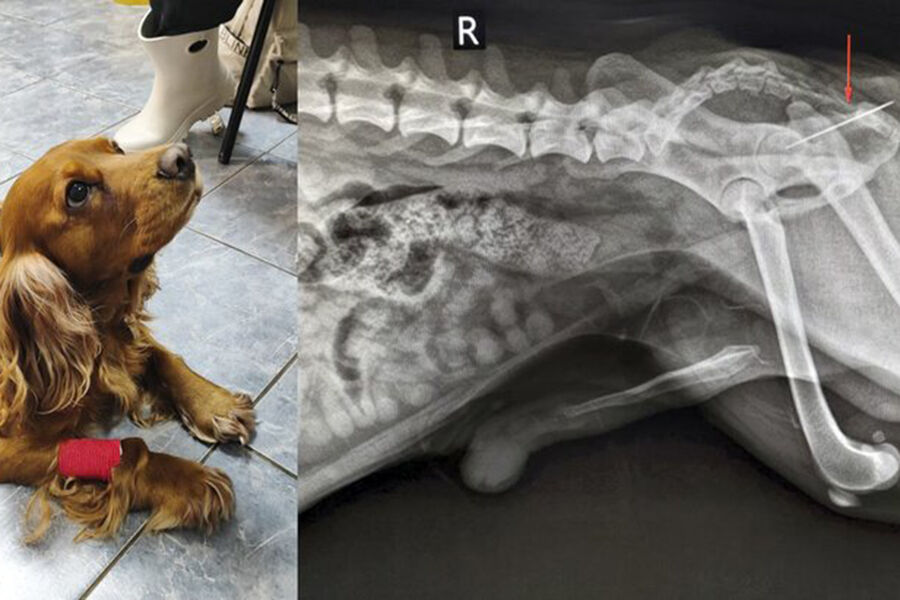

В ветклинике Коптево специалисты спасли собаку породы кокер-спаниель по кличке Вольт, которая проглотила швейную иглу. Об этом «Москве 24» рассказали в столичной госветслужбе.

«При осмотре терапевт Анна Кубатина заметила, что из заднего прохода Вольта торчит швейная нитка. Пациента срочно отправили на рентген», – добавили в пресс-службе.

Врачи установили, что за ниткой тянулась и игла, которая застряла в прямой кишке. Хирург Евгений Бахтин и анестезиолог Светлана Дорожкина провели операцию по извлечению иглы, после этого питомца отпустили домой.